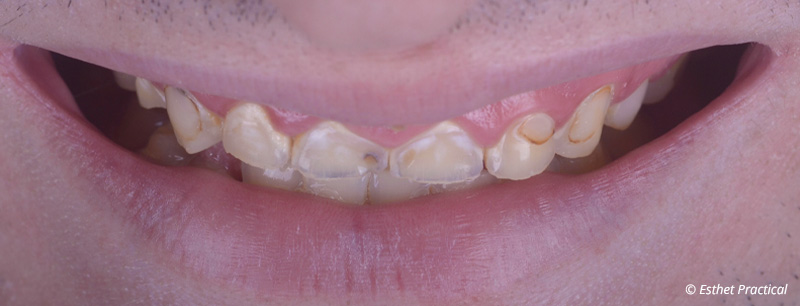

Fig. 01 : situation initiale.

Ce jeune patient consulte pour l’aspect usé de ses dents.

Il se plaint par ailleurs de reflux gastro-œsophagiens, pense serrer les dents et ressent des contractures des mâchoires au réveil. L’étiologie érosive et attritive de l’usure semble donc évidente dans cette situation. L’observation du visage montre des lèvres pincées et un sourire récessif.